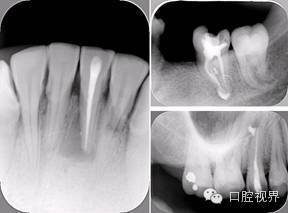

6. 术后 X 线片

术后 X 线片用来评定根管充填 长度、致密度(管壁清晰、侧枝)等指标。

口腔H锉怎么消毒根管治疗的细节把握(细节决定成败)_https://www.jmylbn.com_新闻资讯_第16张

左图为根管充填术后 X 线片。图中可见,根管充填较好。右下图有白色小点,为侧方加压导致糊剂挤出所致,表明根管充填比较致密。

致密、恰到好处的充填可去除干净根管里感染灶,机体逐渐恢复。

多根牙时候需进行偏移投照,正位投照无法说明具体哪根牙根管充填效果。